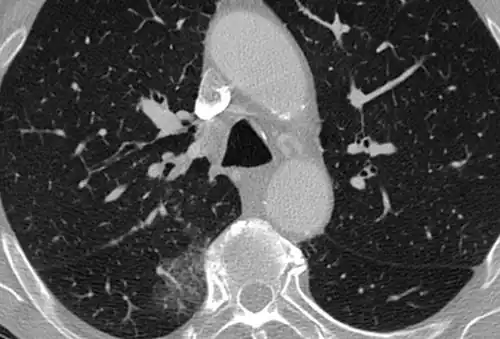

High-Resolution CT image in a patient with Pneumocystis pneumonia infection showing ground-glass opacities.